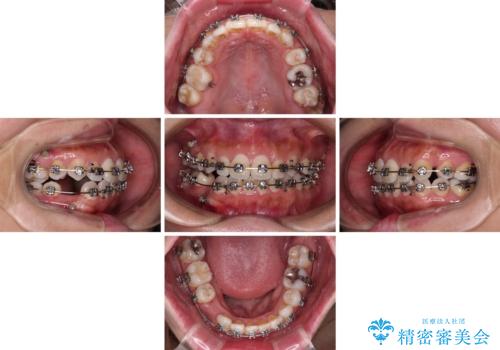

- 矯正装置

- メタルブラケット

- 2年9ヶ月

- 上下前歯のデコボコを気にして来院された患者様です。

右上と左下の小臼歯が1本ずつ欠損しており、奥歯の咬み合わせが乱れている状態でした。

バランスを取るために右下と左上の小臼歯を1本ずつ抜歯し、移動のための固定源としてアンカースクリューを利用してワイヤー装置による矯正治療を行うこととしました。

骨格的な左右差があり、上下正中をぴったり合わせることは難しく、奥歯の咬み合わせの調整にも時間がかかりましたが、きれいに整えることができました。